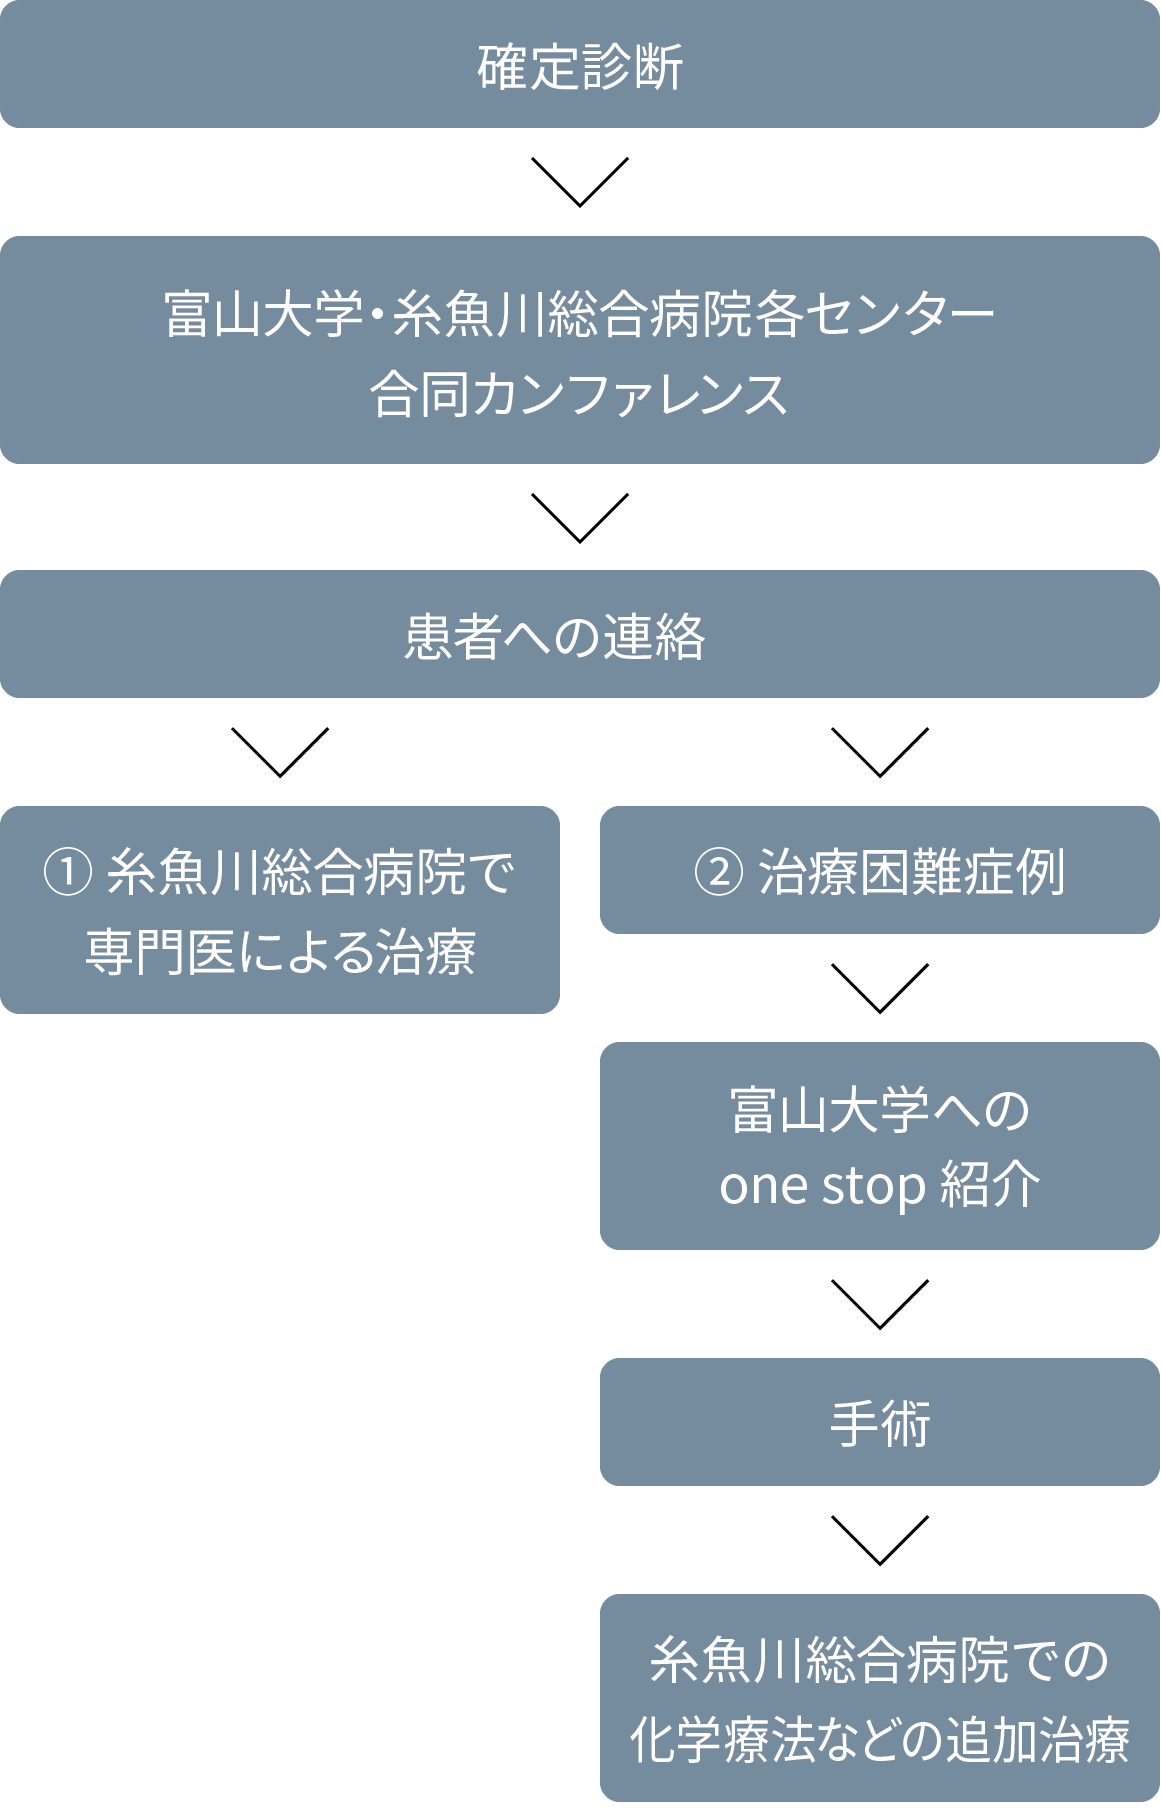

富⼭⼤学附属病院膵臓‧胆道センター‧サテライトとして、富⼭⼤学附属病院で週⼀回開催される肝胆膵キャンサーボード(カンファレンス)にインターネット回線でライブカンファレンス形式で参加し、症例を検討しています。必要な場合には富⼭⼤学附属病院での診断‧治療にもシームレスで移⾏します。

治療進行中は両センター間で治療方針に関しての情報交換が行われ続けます。